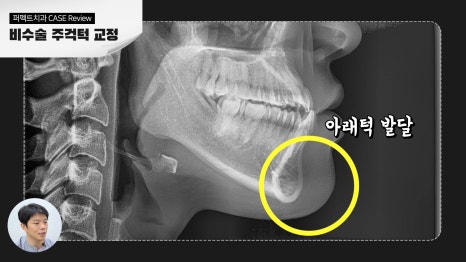

- 하악의 과성장으로 인한 경우

하악이 비정상적으로 과하게 발달하였을 때

주걱턱의 문제가 생기며 모든 주걱턱은

반대교합의 문제를 동반하게 됩니다.